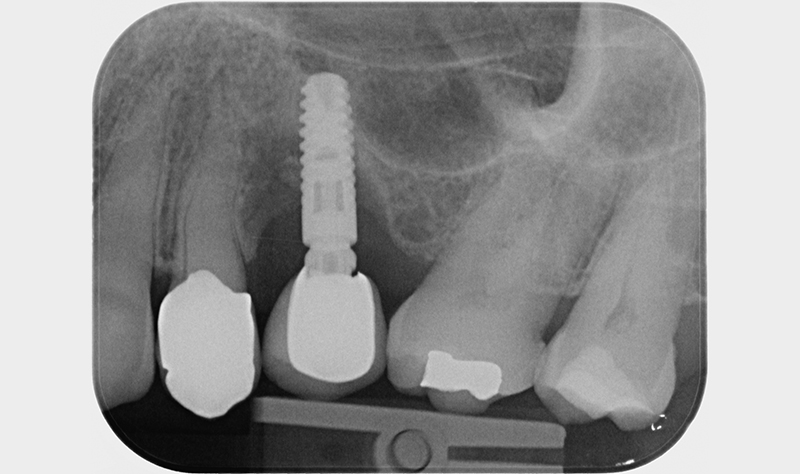

Nell'ultimo anno le è stata riscontrata complicanza a carico dei tessuti peri-implantari di elemento zona 25. L'esame visivo e lo status fotografico (Figs. 1-2) evidenziano un’alterazione dello stato dei tessuti molli peri-implantari, che guida il clinico verso un’indagine più approfondita tramite acquisizione RX. Si esegue perciò esame radiografico del sito coinvolto (Fig. 3), da cui risulta un’importante riassorbimento osseo a carico dell’impianto. Si procede con sondaggio peri-implantare profondo, con la finalità di definire estensione e forma del difetto (Fig. 4) e, associandolo all’esame radiografico, di eseguire la conta delle spire implantari esposte. Tale manovra verrà effettuata con l’impiego di anestetico da irrigazione, data la nota dolorolabilità in peri-implantite, in quanto tale patologia determina la perdita di barriere connettivali e pertanto la penetrazione in osso durante il sondaggio.

RX al baseline

Fig. 3 - Rx al baseline.